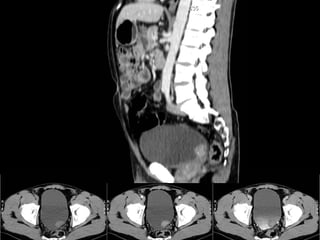

Estudio de Elección:   TC Trifásica Renal  Sin contraste, contraste en fs. arterial, portal y tardía Informa: Comportamiento, tamaño, extensión, número, calcificaciones. Etapificación : compromiso suprarrenal extensión directa a órganos adyacentes adenopatías retroperitoneales invasión de la vena renal y VCI metástasis a distancia (hígado, huesos, cerebro)